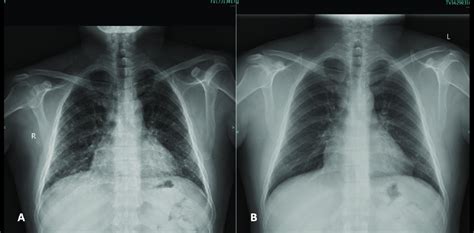

En la radiografía de tórax se reporta la ausencia de lesiones radiológicas o la presencia de infiltrados intersticiales micronodulares.